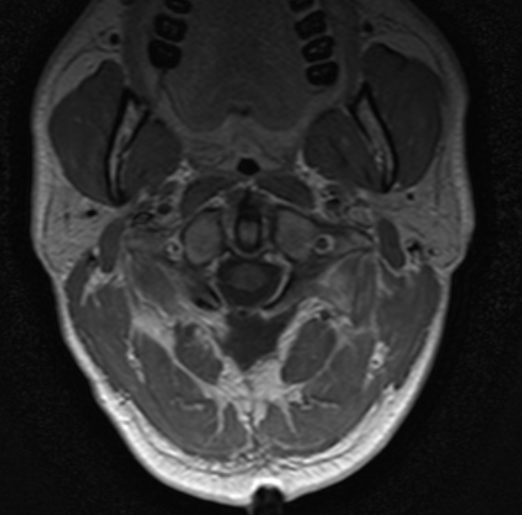

Se realizó un abordaje posterior, con hemilaminectomía derecha de atlas y exéresis de la lesión que parecía adherida al cordón medular a simple vista pero que, tras disección microscópica, pudo identificarse su origen en el segmento más proximal de una radicela del espinal derecho. Tras la exéresis completa, no se constató ningún déficit motor significativo durante la monitorización neurofisiológica intraoperatoria (MNIO) ni en postoperatorio inmediato.